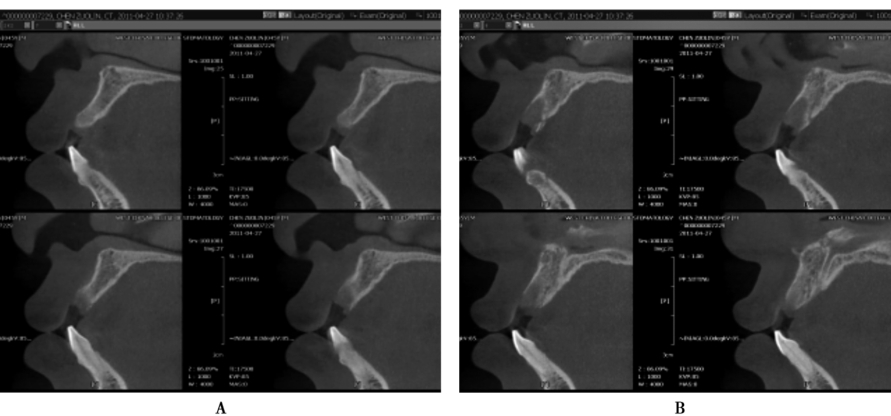

图9 术前术后矢状位CBCT片

A.牙槽骨密度及高度长度均好;B.显示种植体植入后的位置及高度良好

同一个患者前牙区的牙槽骨在不同的位置层面其牙槽骨形状也不一致;

图10 术前CBCT片矢状位显示在不同的层面上颌前牙区的牙槽骨形状不一致